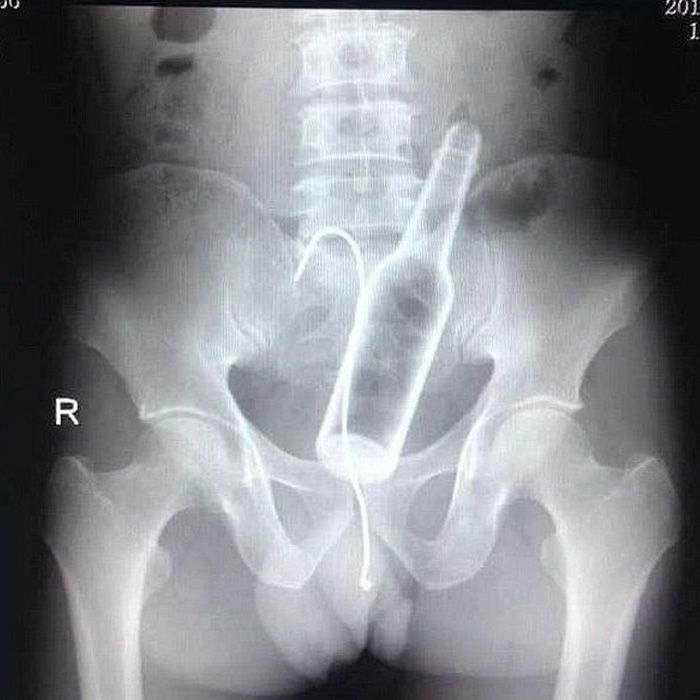

First, someone probably shoved a beer bottle up there (it’s a perfect shape after all). But then it probably got stuck and someone thought it a brilliant idea to use a coat hanger to get it out … and than it got stuck too.